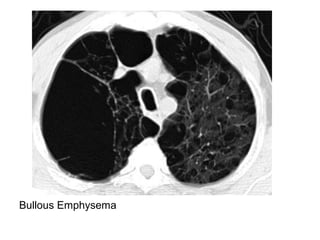

d) Emphysema :

Bullous Emphysema